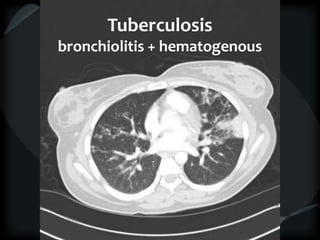

CT features of tuberculosis

 Transbronchial spread – tree-in-bud

 Transbronchial and hematogenous

Tuberculosis

bronchiolitis + hematogenous

TB bronchiolitis + hematogenous